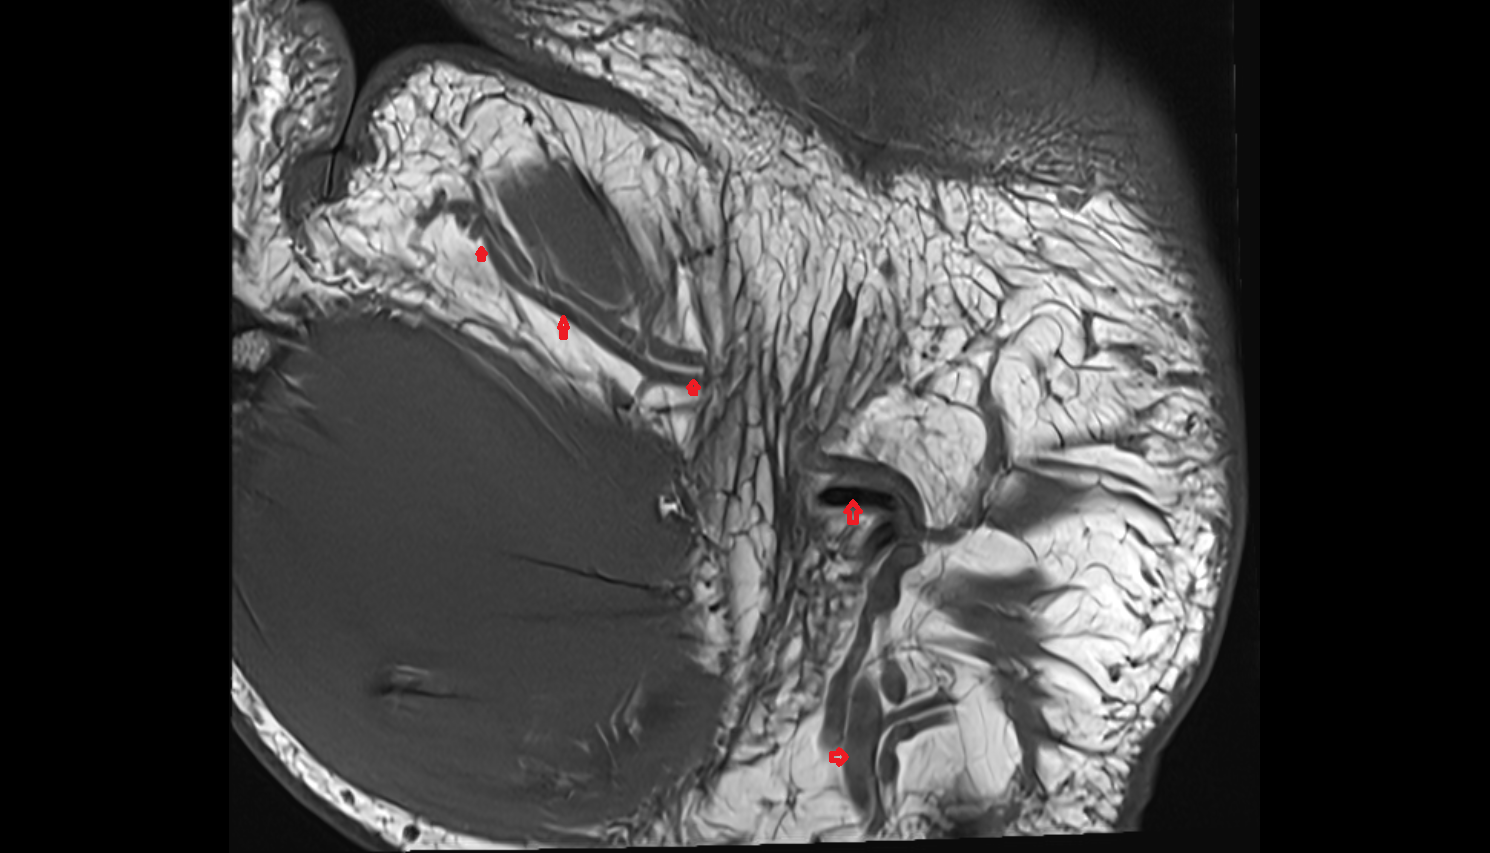

- Temporomandibular joint

- Articular disc of temporomandibular joint

- Articular eminence

- Mandibular condyle

- Mandibular fossa

- Superior head of lateral pterygoid muscle

- Inferior head of lateral pterygoid muscle